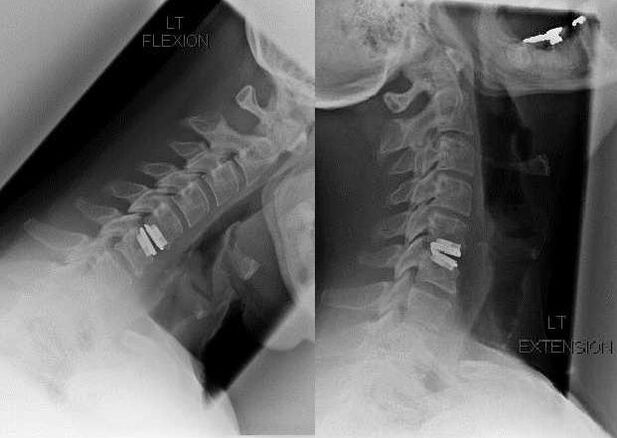

Χειρουργική επέμβαση

Οι ενδείξεις για χειρουργική επέμβαση περιλαμβάνουν την αναποτελεσματικότητα της συντηρητικής θεραπείας και τις επιπλοκές της αυχενικής οστεοχόνδρωσης, για παράδειγμα, δισκογενή μυελοπάθεια, σύνδρομο σπονδυλικής αρτηρίας και ριζικό σύνδρομο. Για την ανακούφιση του φορτίου στο νωτιαίο μυελό, τα αιμοφόρα αγγεία και τις ρίζες της σπονδυλικής στήλης, εκτελούνται οι ακόλουθες επεμβάσεις:

Κατά τη διάρκεια της επέμβασης, τα θραύσματα των οστών και οι σύνδεσμοι μπορούν να αφαιρεθούν και οι μεσοσπονδύλιοι δίσκοι μπορούν να αφαιρεθούν εν όλω ή εν μέρει. Για μικρές προεξοχές κήλης, συχνά εκτελείται εξάτμιση με λέιζερ του πυρήνα του δίσκου.

Μετά την αφαίρεση των σπονδυλικών δομών, συχνά απαιτείται σταθεροποίηση των τμημάτων κίνησης της σπονδυλικής στήλης μέσω σπονδυλικής σύντηξης ή εγκατάστασης αυτομοσχευμάτων οστού και δέρματος.